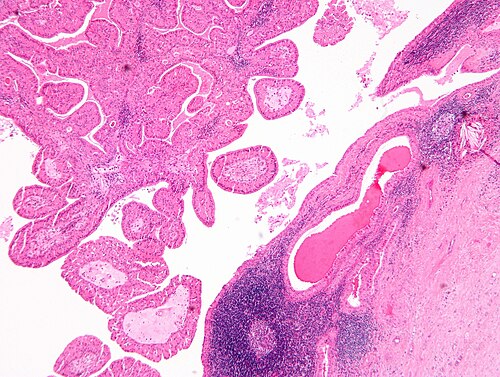

59 year old man, mass lesion

Site

Left parotid

Primary image

Low magnification. H&E stain.